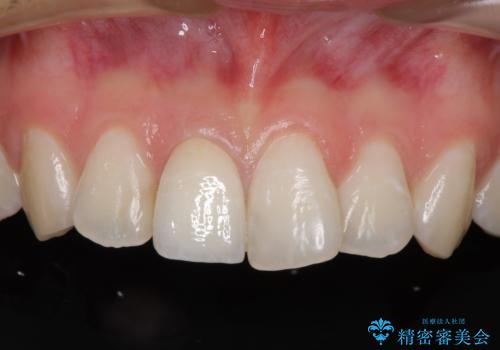

変色した歯をセラミックにしたい 歯自体が変色している場合の参考用2

歯は神経をとると、だんだん黒くなることがあります。今回はセラミックで歯を覆うことにより、見た目の改善を図りました。

患者様のご希望で、最終的な色を決める前に、ホワイトニングをしました(約3万円)。ただし、ホワイトニング直後は色が白くなりすぎる等の恐れがあるため、色が落ち着くのを待ってからセラミックを製作しました。